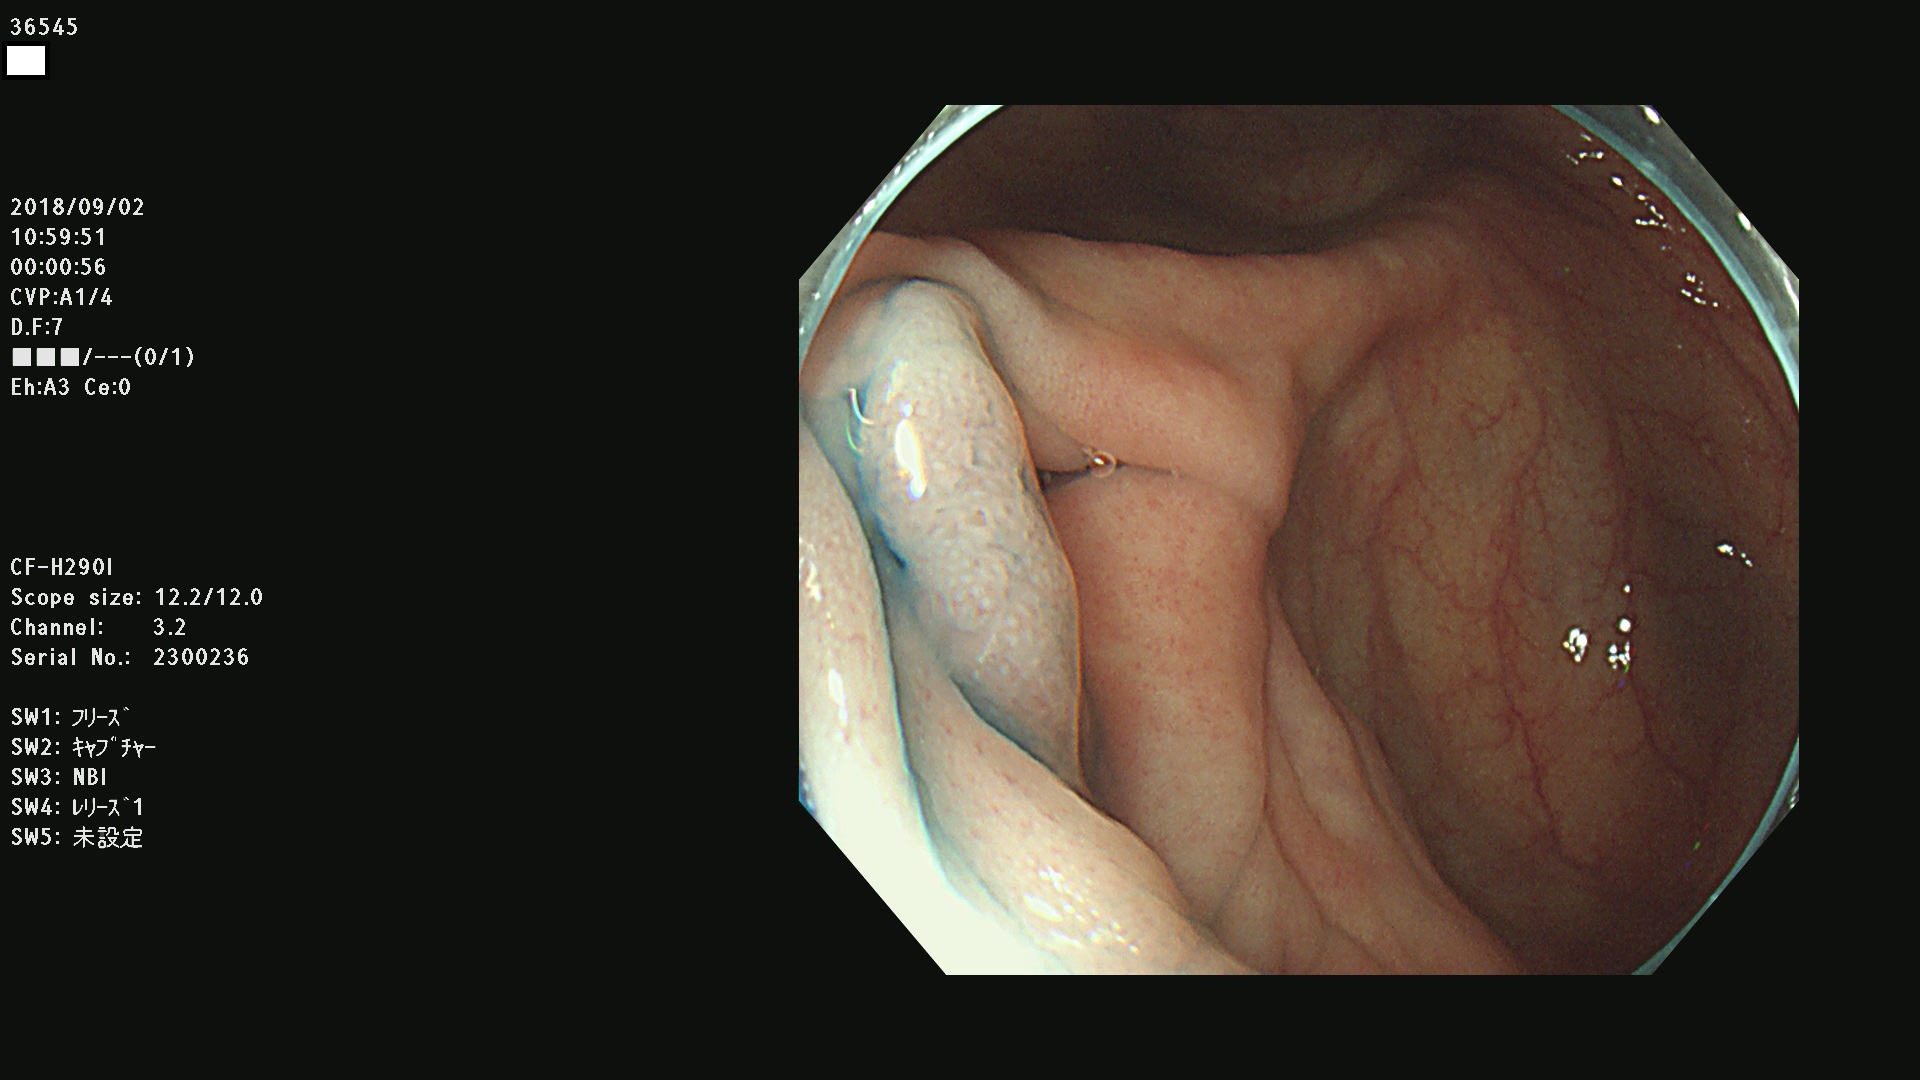

36500 36503 36504 36505 36507(SSAPのみ) 36508 36509 36510 36511 36514 36515 36517 36518 36520 36522(SSAPのみ) 36523 36524 36526 36528 36530 36531 36532 36533 36534 36535 36536 36538 36541 36542 36543 36544 36545 36546 36548 36550 36551 36554 36555 36556 36558 36559 36560 36561 36564 36565 36567 36568 36570 36572 36573 36574 36575 36576 36577 36578 36579 36580 36582 36584 36586 36591 36592 36593 36594 36595 36596 36597 36598

発見困難で危険性の高い平坦型病変(上記100名より抽出)

虫垂SSAP